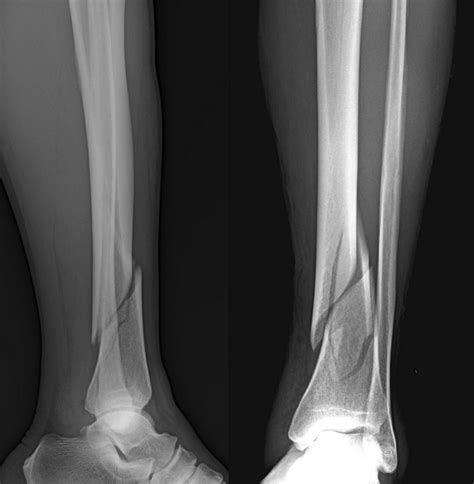

Diagnosing a Broken Fibula and Tibia

Diagnosing a fracture involves a combination of physical examination and imaging tests. The process typically includes:

• Physical Examination: A healthcare provider will assess the injured area for swelling, deformity, and tenderness.

• X-rays: These are the primary imaging tool used to confirm the presence and type of fracture.

Symptoms of a Broken Fibula and Tibia

Recognizing the symptoms of a fibula and tibia broken is crucial for prompt medical intervention. Common symptoms include:

• Deformity or visible misalignment of the leg.